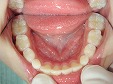

小児歯科

治療前に歯科器材や治療行為に慣れるためのトレーニングを行い、お子さんが泣かない、そして笑顔で治療が終えられるように心がけています。ただし外傷・歯髄炎・根尖性歯周炎など痛みを伴う緊急時は、トレーニングを行いながらの治療は難しい場合もあります。また永久歯に萌えかわる時期は、むし歯になりやすいため予防処置(フッ素塗布等)・シーラント(予防填塞)をおすすめします。

~シーラント~

術前

術後